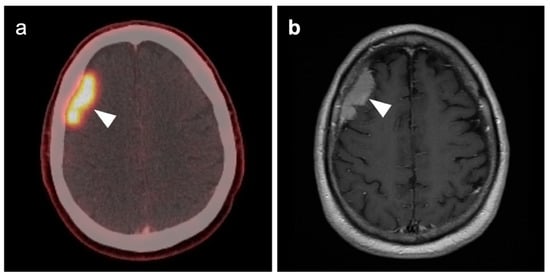

3.5. Brain Metastases